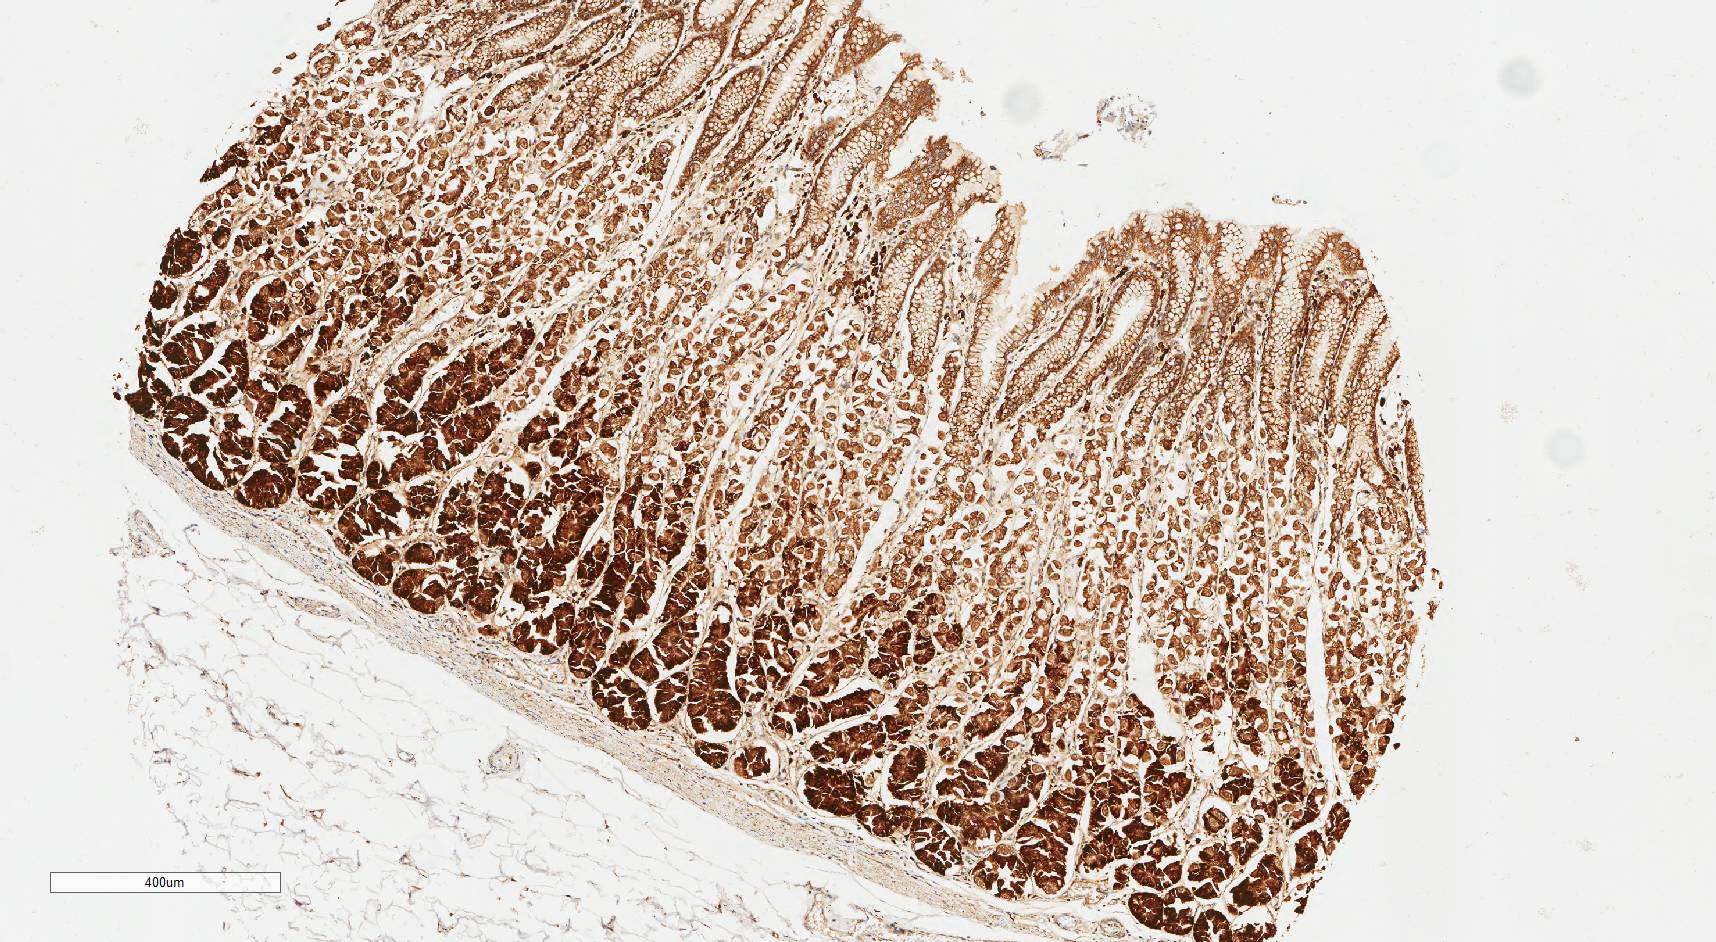

Laminin N terminus alpha31 (LaNt a31) is a really interesting laminin-related protein that the Hamill lab has been investigating for a while. Until recently, our studies focused entirely on the epithelial tissues of the skin, the surface of the eye and oral squamous cell carcinoma. However, we’ve always known that this relatively unstudied protein is also expressed by other tissues. As a first (and really important) step to understanding what this protein’s role is in tissue function, we used our new mouse monoclonal antibodies against the human form of LaNt a31 to screen a wide-range of human tissues.

Below you can see some of our favourite images from the selection. Click on an image to view as a slideshow.

You can see the whole story in the paper by Lee Troughton et al., available here.